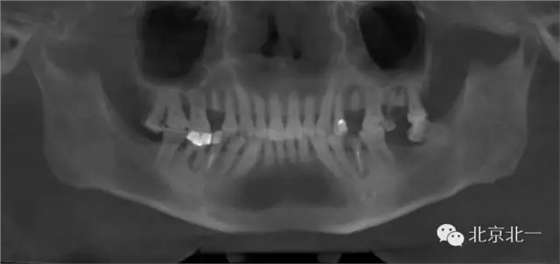

1.難度預(yù)判:拔牙前了解需拔除患牙情況及其與鄰牙、周圍組織的關(guān)系 術(shù)前影像學(xué)檢查了解牙齒形態(tài)、結(jié)構(gòu)及其與周圍重要解剖結(jié)構(gòu),如上頜竇、下頜神經(jīng)管等的位置關(guān)系。術(shù)前與患者及家屬交代拔牙過程及術(shù)中、術(shù)后的相關(guān)事項(xiàng),以緩解患者的緊張、恐懼心理,取得其信任與配合。

其他區(qū)域埋伏牙(多生牙、尖牙、前磨牙、上頜第三磨牙)首先根據(jù)影像學(xué)選擇正確的手術(shù)人路,翻瓣及去除覆蓋牙冠骨組織,顯露患牙牙冠,然后通過增隙或分割,遵循“化整為零”的微創(chuàng)理念取出患牙。